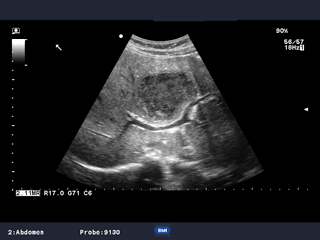

当社ハイエンド装置で培った技術・機能を継承しながら,小型軽量化により可搬性を向上させた超音波診断装置です。

プロサウンドα7 は,高性能の装置は大きいという常識をくつがえした,パワフルでやさしく,コンパクトな超音波診断装置です。上位機種で培った設計思想を踏襲し,コントラスト分解能・空間分解能に優れた画像を提供します。サイドローブの低減と高いS/N比によって画像上に不要な情報が少なく,診断しやすくなっています。検査者の疲労軽減と検査効率向上のために使いやすさを追求。検査時間の短縮は患者様の負担も軽減します。さらに,エコロジーに配慮した素材の使用,低消費電力など,環境へのやさしさも配慮されています。